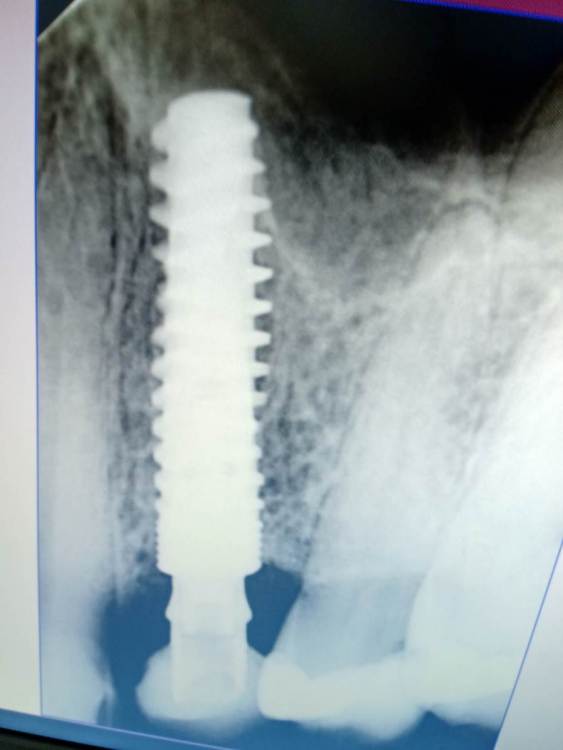

BORA Опубликовано 10 апреля, 2021 Поделиться Опубликовано 10 апреля, 2021 Здравствуйте коллеги.Подскажите пожалуиста систему имплантатов.Подходит отвёртка Osstem к винту,трансфера mini и regular нет. На ресурсе всеимпланты.нашел похожее. Ссылка на комментарий

Irouil Опубликовано 11 апреля, 2021 Поделиться Опубликовано 11 апреля, 2021 Чем же, интересно, они похожи? На верхнем снимке Анкилос, судя по всему, временная коронка тоже на его темп-бейзе слеплена, а на нижнем снимке плоскостной винт Ссылка на комментарий

АнтонТЛТ Опубликовано 11 апреля, 2021 Поделиться Опубликовано 11 апреля, 2021 3 часа назад, Irouil сказал: Чем же, интересно, они похожи? На верхнем снимке Анкилос, судя по всему, временная коронка тоже на его темп-бейзе слеплена, а на нижнем снимке плоскостной винт У анкилоза нет микрорезьбы на шейке, отвертка 0.9 (1.0)мм, у осстема 1.2мм. винты из абатментов вроде не вынимаются, да и позиционер другой. 1 Ссылка на комментарий

Irouil Опубликовано 12 апреля, 2021 Поделиться Опубликовано 12 апреля, 2021 Ай, больно!) Тем не менее, конус, и достаточно глубокий. Ссылка на комментарий